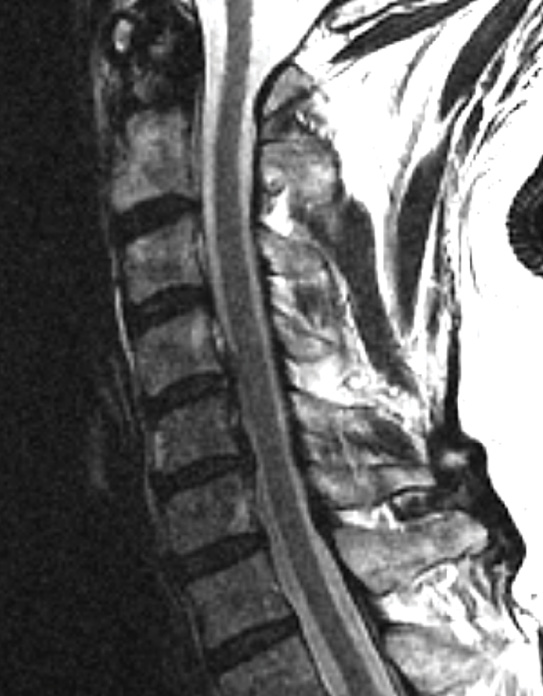

MRIs illustrated mild degenerative disc disease from C4-6 with disc herniations at both C4-5 and C5-6. The axial slice through C4-5 showed a right central disc herniation causing central and mainly right-sided foraminal stenosis. The axial slice through C5-6 showed a central disc herniation also causing central and mainly right-sided foraminal stenosis. The axial slice through C6-7 showed a left-sided disc herniation causing some left-sided foraminal stenosis, however, the patient did not demonstrate any left-sided symptoms.

Upon examination, the patient had good motion on flexion-extension, so fusion was not considered at all. My operative plan was to use prodisc cervical devices and replace both discs at C4-5 and C5-6, giving me the flexibility to use either a domed or flat implant.